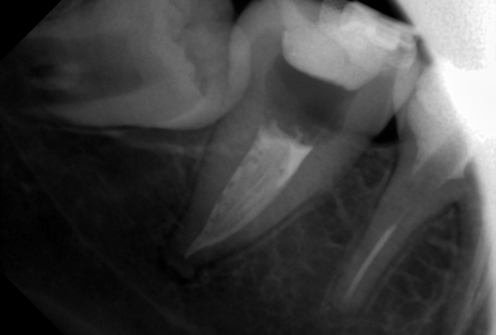

В стоматологической клинике "5 Принципов" в Симферополе мы гордимся тем, что каждый пациент получает индивидуальный подход и безупречный результат в области эндодонтического лечения под микроскопом. Наши специалисты применяют современные цифровые технологии, микропроцессорные и нейромодуляционные инструменты, что позволяет достичь максимальной точности и минимального дискомфорта. В портфолио клиники — широкий спектр кейсов: от первичной диагностики пульпита до сложной ретенированной резорбции и повторной эндодонтии. Мы беремся за зубы любых степеней сложности: от моляра до резцов, используя щадящие концевые инструменты и безболезненные методы постоянной анестезии. Все процедуры проходят под увеличением, что обеспечивает точное удаление инфицированной ткани и сохранение естественной анатомии зуба.Особое внимание мы уделяем постпроцедурному наблюдению: контроль за герметичностью заполнения корневых каналов, профилактические рекомендации и возможная корректировка плана лечения при необходимости. В "5 Принципах" мы разумно сочетаем комфорт, эстетическую привлекательность и долгосрочную функциональность. Результат — здоровые зубы, уверенная улыбка и спокойствие наших пациентов в Симферополе. Запишитесь на консультацию и убедитесь сами в нашем подходе к качественному эндодонтическому лечению.